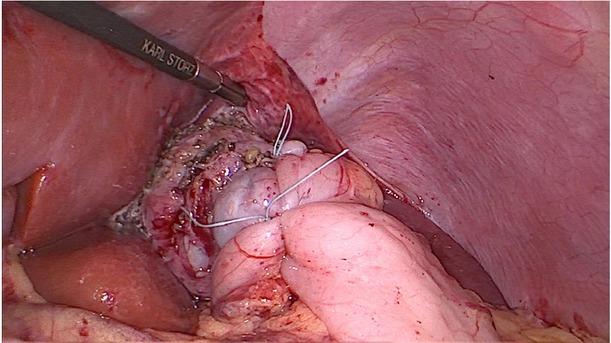

Figure 3